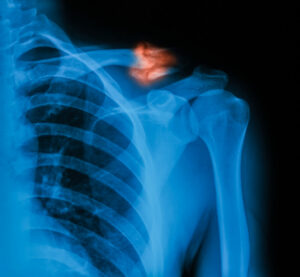

Finding the Best Separated Shoulder Treatment Near You

A separated shoulder can be a painful and challenging injury that interferes with everyday tasks and physical activities. Whether you sustained this injury during a sports activity or an accidental fall, finding the right treatment is essential for recovery. In this blog, we will explain what a [Read More]

Best Broken Collarbone Treatment Near Me

A broken collarbone, also known as a clavicle fracture, is a common injury seen in sports and everyday accidents. It can result from a fall, a direct hit during contact sports, or even a vehicle collision. Regardless of the cause, a broken collarbone can lead to significant discomfort and [Read More]